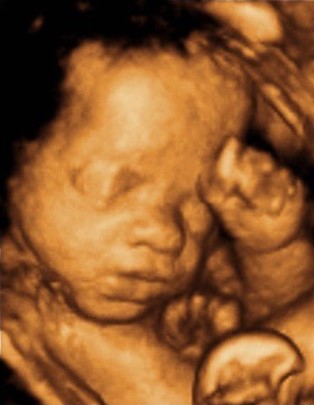

Results Showcase

Facial structure

Profile view

Hand detail

Full body

Foot geometry

Head topology